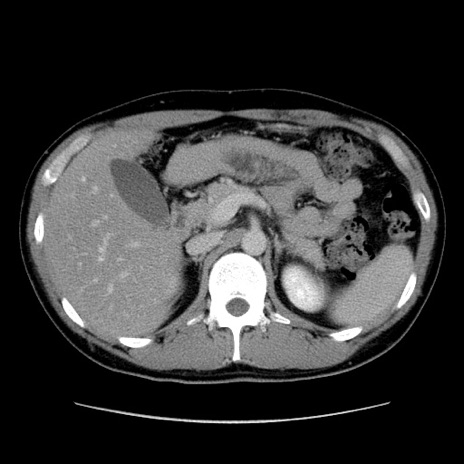

症例36(横断像)

【症例】20歳代 男性

【主訴】心窩部痛

【現病歴】今朝より上腹部痛あり。一旦軽快していたが再度出現したため救急要請。昨日夕に白身の魚を含む刺身を食べた。

【身体所見】BP 136/89mmHg、HR 74/min、BT 37.0℃、腹部:膨満、軟、心窩部に圧痛あり。反跳痛なし、筋性防御なし、腸雑音やや亢進あり。

【データ】WBC 17700、CRP 0.48